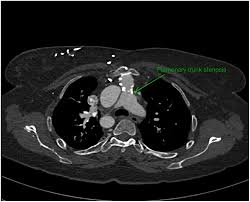

In radiology, diagnostic imaging requires specialized knowledge to interpret the findings associated with a wide variety of diseases. Fortunately, in recent years, generative AI models, such as Chat Generative Pre-trained Transformer (ChatGPT), have shown potential as diagnostic tools in the medical field, but their accuracy must be evaluated for optimal use in the future.